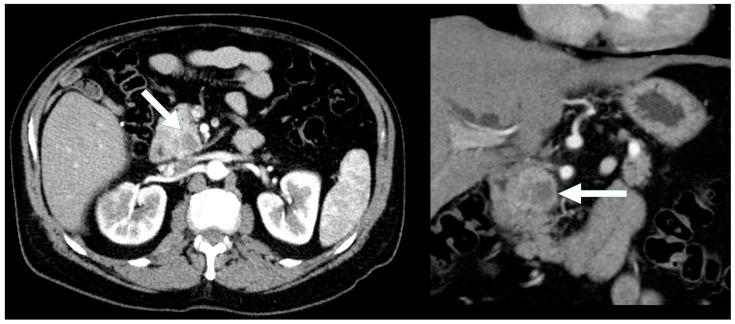

Pancreatic neuroendocrine neoplasms (PNENs) are rare but clinically significant tumors with variable radiological presentations that complicate diagnosis. While typical PNENs are well characterized, atypical features, such as cystic or hypoenhancing patterns, are less understood and can lead to diagnostic delays or misdiagnosis. This study aimed to evaluate atypical radiological presentations of PNENs, focusing on their impact on diagnostic pathways and differentiation from other pancreatic pathologies. A retrospective review was conducted of all PNEN cases diagnosed at a single tertiary center between 2010 and 2020. Cases with histopathological confirmation and available cross-sectional imaging were included. Radiological features were categorized as typical (solid and hyperenhancing) or atypical (cystic and hypoenhancing). Demographic, radiological, and pathological data were analyzed. Comparisons between typical and atypical PNENs were performed using descriptive and inferential statistics. Among 77 PNEN cases, 39 met the inclusion criteria. Atypical radiological presentations were identified in 46% of cases, including cystic (18%) and hypoenhancing (28%) lesions. Hypoenhancing PNENs were significantly more likely to present with advanced disease (54% vs. 14% in typical PNENs, = 0.016). In contrast, none of the cystic PNENs exhibited advanced disease. Atypical PNENs posed greater diagnostic challenges, with alternative diagnoses initially considered in 64% of hypoenhancing and 43% of cystic cases compared to 10% of typical PNENs ( = 0.0042). Atypical PNENs, particularly hypoenhancing lesions, present significant diagnostic challenges and are more likely to be associated with advanced disease. These findings highlight the need for improved recognition of atypical imaging patterns and more precise diagnostic strategies. However, the retrospective design and small cohort size limit the generalizability of our findings. Further multicenter studies are warranted to refine the imaging criteria and optimize the differentiation from other pancreatic neoplasms.

胰腺神经内分泌肿瘤(PNENs)虽罕见,但具有临床意义,其放射学表现多样,使诊断变得复杂。典型的PNENs特征明确,但非典型特征,如囊性或强化减弱模式,了解较少,可能导致诊断延迟或误诊。本研究旨在评估PNENs的非典型放射学表现,重点关注其对诊断途径的影响以及与其他胰腺病变的鉴别。对2010年至2020年在单个三级中心诊断的所有PNEN病例进行了回顾性研究。纳入有组织病理学证实且有横断面影像资料的病例。放射学特征分为典型(实性且强化明显)或非典型(囊性且强化减弱)。对人口统计学、放射学和病理学数据进行分析。使用描述性和推断性统计对典型和非典型PNENs进行比较。在77例PNEN病例中,39例符合纳入标准。46%的病例发现有非典型放射学表现,包括囊性病变(18%)和强化减弱病变(%)。强化减弱的PNENs出现晚期疾病的可能性显著更高(54%,而典型PNENs为14%,P = 0.016)。相比之下,囊性PNENs均未出现晚期疾病。非典型PNENs带来更大的诊断挑战,与典型PNENs的10%相比,64%的强化减弱病例和43%的囊性病例最初考虑了其他诊断(P = 0.0042)。非典型PNENs,尤其是强化减弱病变,带来显著的诊断挑战,且更可能与晚期疾病相关。这些发现凸显了提高对非典型影像模式的认识以及采用更精确诊断策略的必要性。然而,回顾性设计和小样本队列限制了我们研究结果的普遍性。有必要进行进一步的多中心研究以完善影像标准并优化与其他胰腺肿瘤的鉴别。